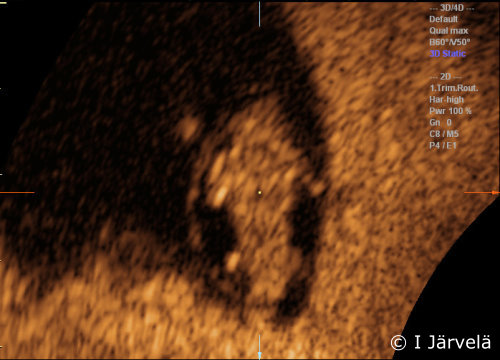

Pregnancy Week 7: Limb Buds (Ultrasound Scan)

Pregnancy week 7: limb buds (ultrasound scan). Limb buds are visible in the 7th week of pregnancy.

Picture: Ilkka Järvelä; text: Dimitrios Scordas